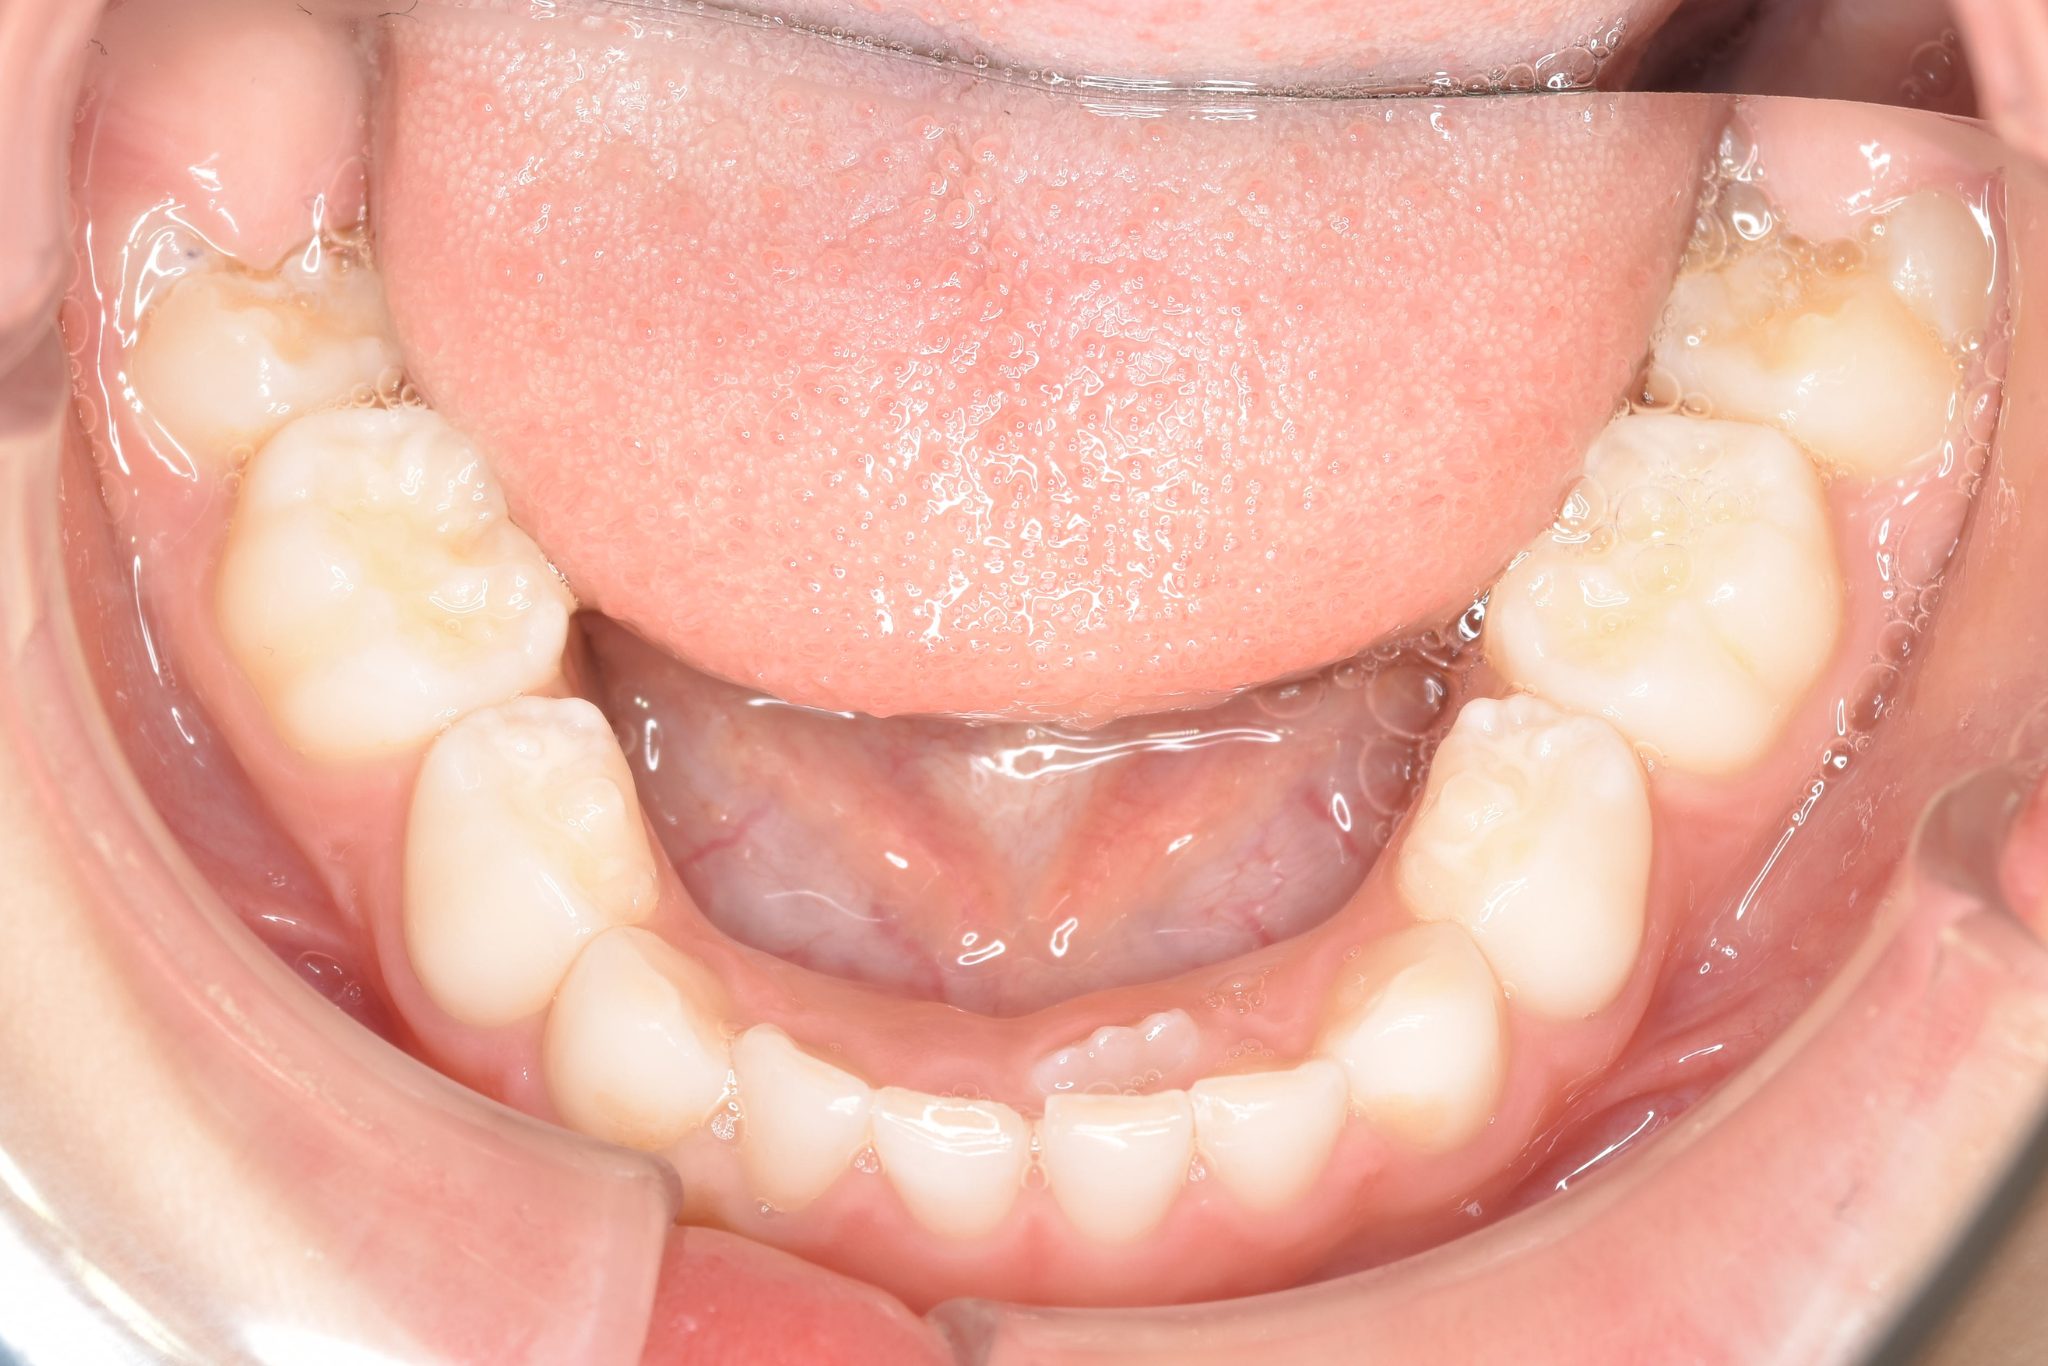

ビフォー

子どもの矯正治療|症例_121

主訴 歯並び

施術内容 上顎急速拡大装置と下顎リンガルアーチを用いて上下顎骨を拡大した。

その後マウスピース型矯正装置で歯牙を配列し良好な咬合を獲得した。

治癒期間 3年11ヶ月間